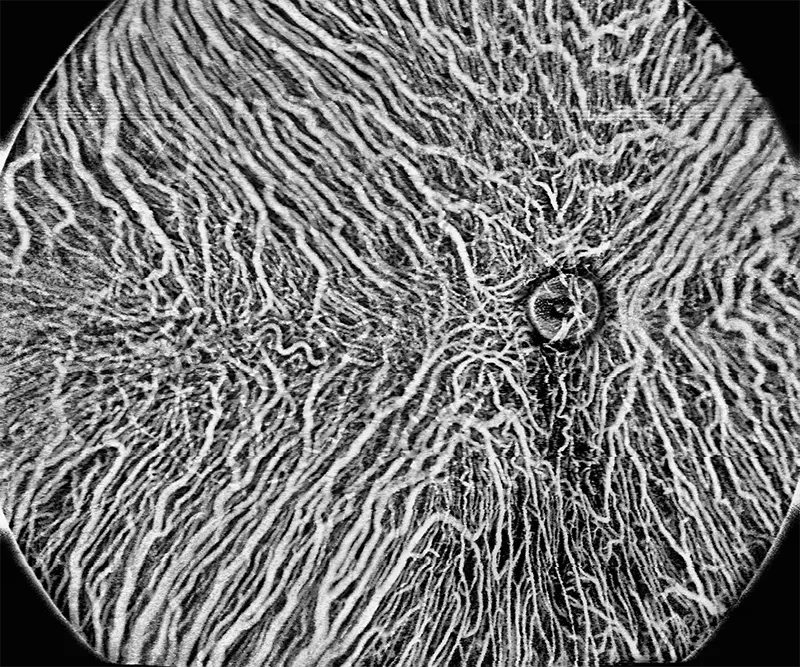

BMizar (BM-400K) es el OCT más potente de la industria con una fuente de barrido de 400 kHz. Su excepcional diseño óptico eleva la experiencia de la Angiografía OCT a un nivel sin precedentes. Con imágenes de alta definición de la retina, la coroides y el segmento anterior, cubre sin esfuerzo un área increíblemente grande en un solo escaneo (logrando un OCTA de 24 mm de ancho en solo 7-15 segundos).

Galería OCTs del TowardPi BMizar